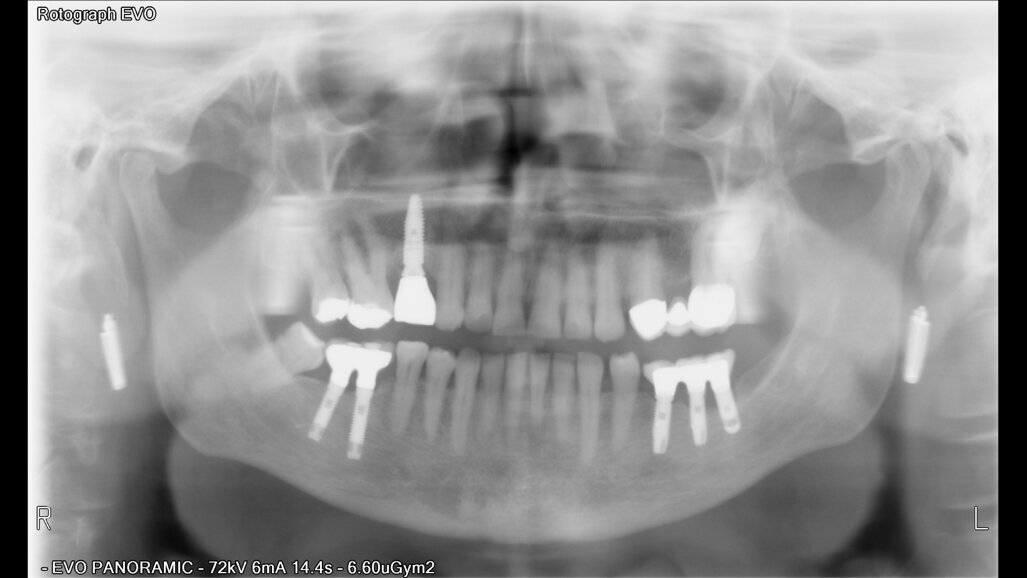

Posuzovali jsme 181 pacientů (97 žen a 121 mužů s průměrným věkem 49,2 let) se 721 implantáty. Z toho bylo zavedeno 384 implantátů na úrovni kosti, 289 zúžených implantátů na úrovni kosti a 48 implantátů na úrovni měkkých tkání (tabulka 2). Implantáty byly klasifikovány podle jejich pozice v horní a dolní čelisti. Pokud jde o anamnézu kouření u pacientů, počet denně vykouřených cigaret se pohyboval mezi 20 a 60 cigaretami.

Po chirurgickém zákroku byly pořízeny periapikální RTG snímky, na nichž byla zkontrolována přesnost zavedení implantátů. Pooperační medikace spočívala v předepsání antibiotik. Digitální RTG snímky byly pořízeny v době chirurgického zákroku, po 24 hodinách a jeden měsíc po zákroku, a to za účelem vyhodnocení úspěšnosti implantologického ošetření. Zánětlivé procesy byly zjištěny u 24,1 % pacientů. V případě potřeby byla provedena augmentace za použití materiálu NanoBone (Artoss), kostní náhražky Geistlich Bio­Oss a membrán Geistlich Bio-Gide (oba produkty Geistlich Biomaterials).

Ze 721 implantátů selhalo celkem 65 implantátů. Míra úspěšnosti tedy ve výsledku byla 90,98 %, tedy nižší než v naší předchozí studii provedené u nekuřáků, u nichž byla míra úspěšnosti 98,70 %.2 U skupiny neúspěšných implantátů selhala většina z nich (74,5 %) dva až čtyři týdny po zavedení v důsledku nedostatečné oseointegrace. Periimplantitida se vyskytovala u 20 % neúspěšných implantátů. To lze přičíst špatné ústní hygieně a tvorbě plaku. U 4,6 % případů se periimplantitida objevila v rozmezí jednoho až tří let po zavedení implantátu v důsledku mechanických problémů po úbytku kosti. Nebyla zjištěna žádná souvislost mezi délkou a průměrem implantátu a mírou selhání, ani mezi počtem vykouřených cigaret a mírou selhání implantátu.

Implantologické ošetření je jednoznačnou volbou pro ošetření pacientů s chybějícími zuby. Některé stavy, jako je kouření, hypertenze a diabetes, však mají na úspěšnost dentálních implantátů negativní vliv. Bylo zjištěno, že nikotin způsobuje osteoklastické změny. Na základě zde popsaných případů a výsledků u dalších pacientů lze dojít k závěru, že v současné době je možno dosáhnout dobrých výsledků i u silných kuřáků. Je obtížné vyhodnotit roli jednoho rizikového faktoru, jako je kouření, ve vztahu k dobrým výsledkům implantologického ošetření, protože se u mnoha pacientů vyskytují i další rizikové faktory zahrnující diabetes, pokročilý věk nebo nízkou hustotu kosti. Navíc jsou u kuřáků značné rozdíly, pokud jde o skutečný počet denně vykouřených cigaret a let, po které pacient kouří. Na úspěšnost oseointegrace kromě toho může mít vliv pozice implantátů, a zda jsou zavedeny v horní nebo dolní čelisti. U kuřáků totiž dochází k většímu úbytku okrajové kosti kolem implantátů v horní čelisti. Příčina selhání implantátu se tedy může lišit i s ohledem na umístění implantátu v souvislosti s kvalitou a množstvím alveolární kosti, do které je implantát zaveden. Každá alveolární kost se také liší z hlediska minerální hustoty, mikrostruktury a tloušťky trabekulární kosti.